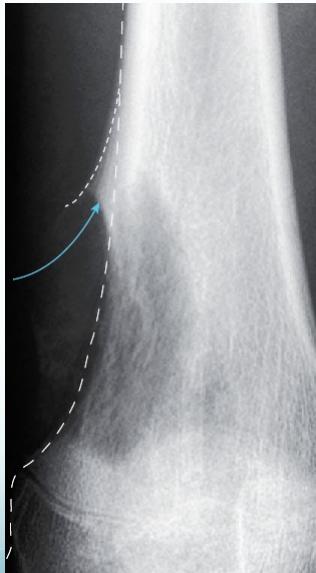

Radiological Features

- X-ray:

- Radiolucency and sclerosis

- Poorly defined margins

- Extends into soft tissue

- Periosteal reaction:

- Sunburst (sun-ray) appearance

- Codman’s triangle